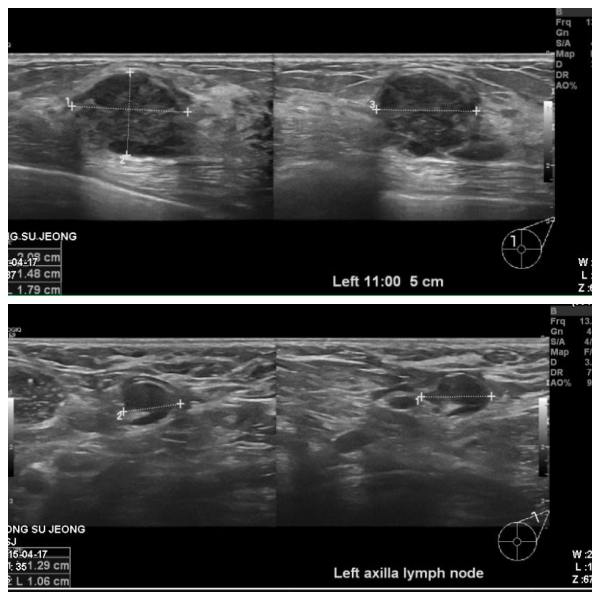

좌측유방에 만저지는 몽우리 있어 내원하신 30대 여성분으로 좌측 침윤성유관암 진단받으셨고, 겨드랑이 전이로 확인 되었습니다